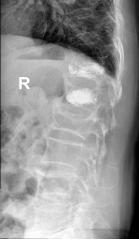

70岁的梁奶奶,家人说老人家因提重物导致腰背疼痛,正因疫情期间,在家休息仍无缓解,因疼痛无法正常生活,迫于为梁奶奶解除痛苦,居家7天后家人带其来到我院就诊,张昊主任医师阅读了相关影像学资料,经过团队的讨论,首先明确诊断为 “1.胸12、腰1椎体压缩性骨折 2.重度骨质疏松症”。针对老年人骨质疏松导致椎体压缩性骨折的治疗,把相关治疗方案以及相应的风险等事宜详细告知家属,最终采用经皮穿刺椎体后凸成形术为梁奶奶进行手术,术后疼痛明显缓解,效果非常满意,第二天顺利出院。

术前影像

术后影像